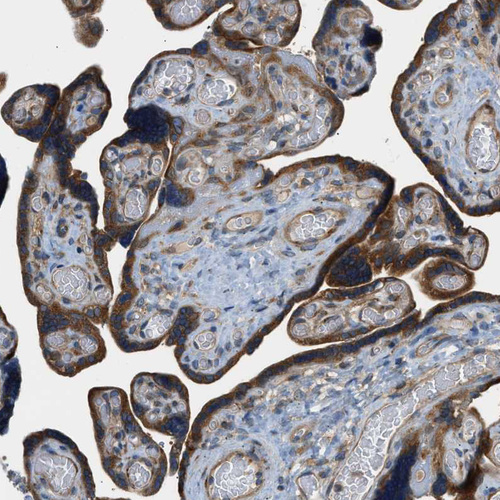

Immunohistochemical staining of human urinary bladder shows strong cytoplasmic positivity in urothelial cells.